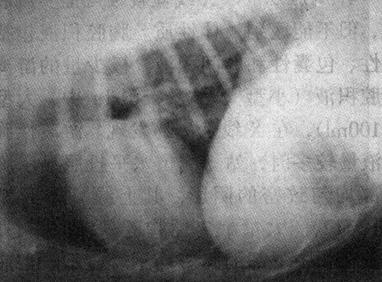

7)腐蹄病 X线表现为蹄部软组织肿胀、密度增浓。如软组织腐败溃破或形成瘘管后,可见有半圆形密度降低的透明区和液平面。蹄关节间隙因关节腔内的渗出和积脓而增宽。如关节囊破坏后,蹄关节呈半脱位或脱位。第二、三指(趾)常出现骨质破坏。有些病例蹄尖部骨质破坏,形成大的缺损。因感染可引起广泛性骨化性骨膜炎(图1-7)。

图1-7 牛腐蹄病

背跖位显示一侧蹄关节软组织肿胀,关节缘骨质破坏,广泛性骨膜新骨增生,蹄骨外侧脱位